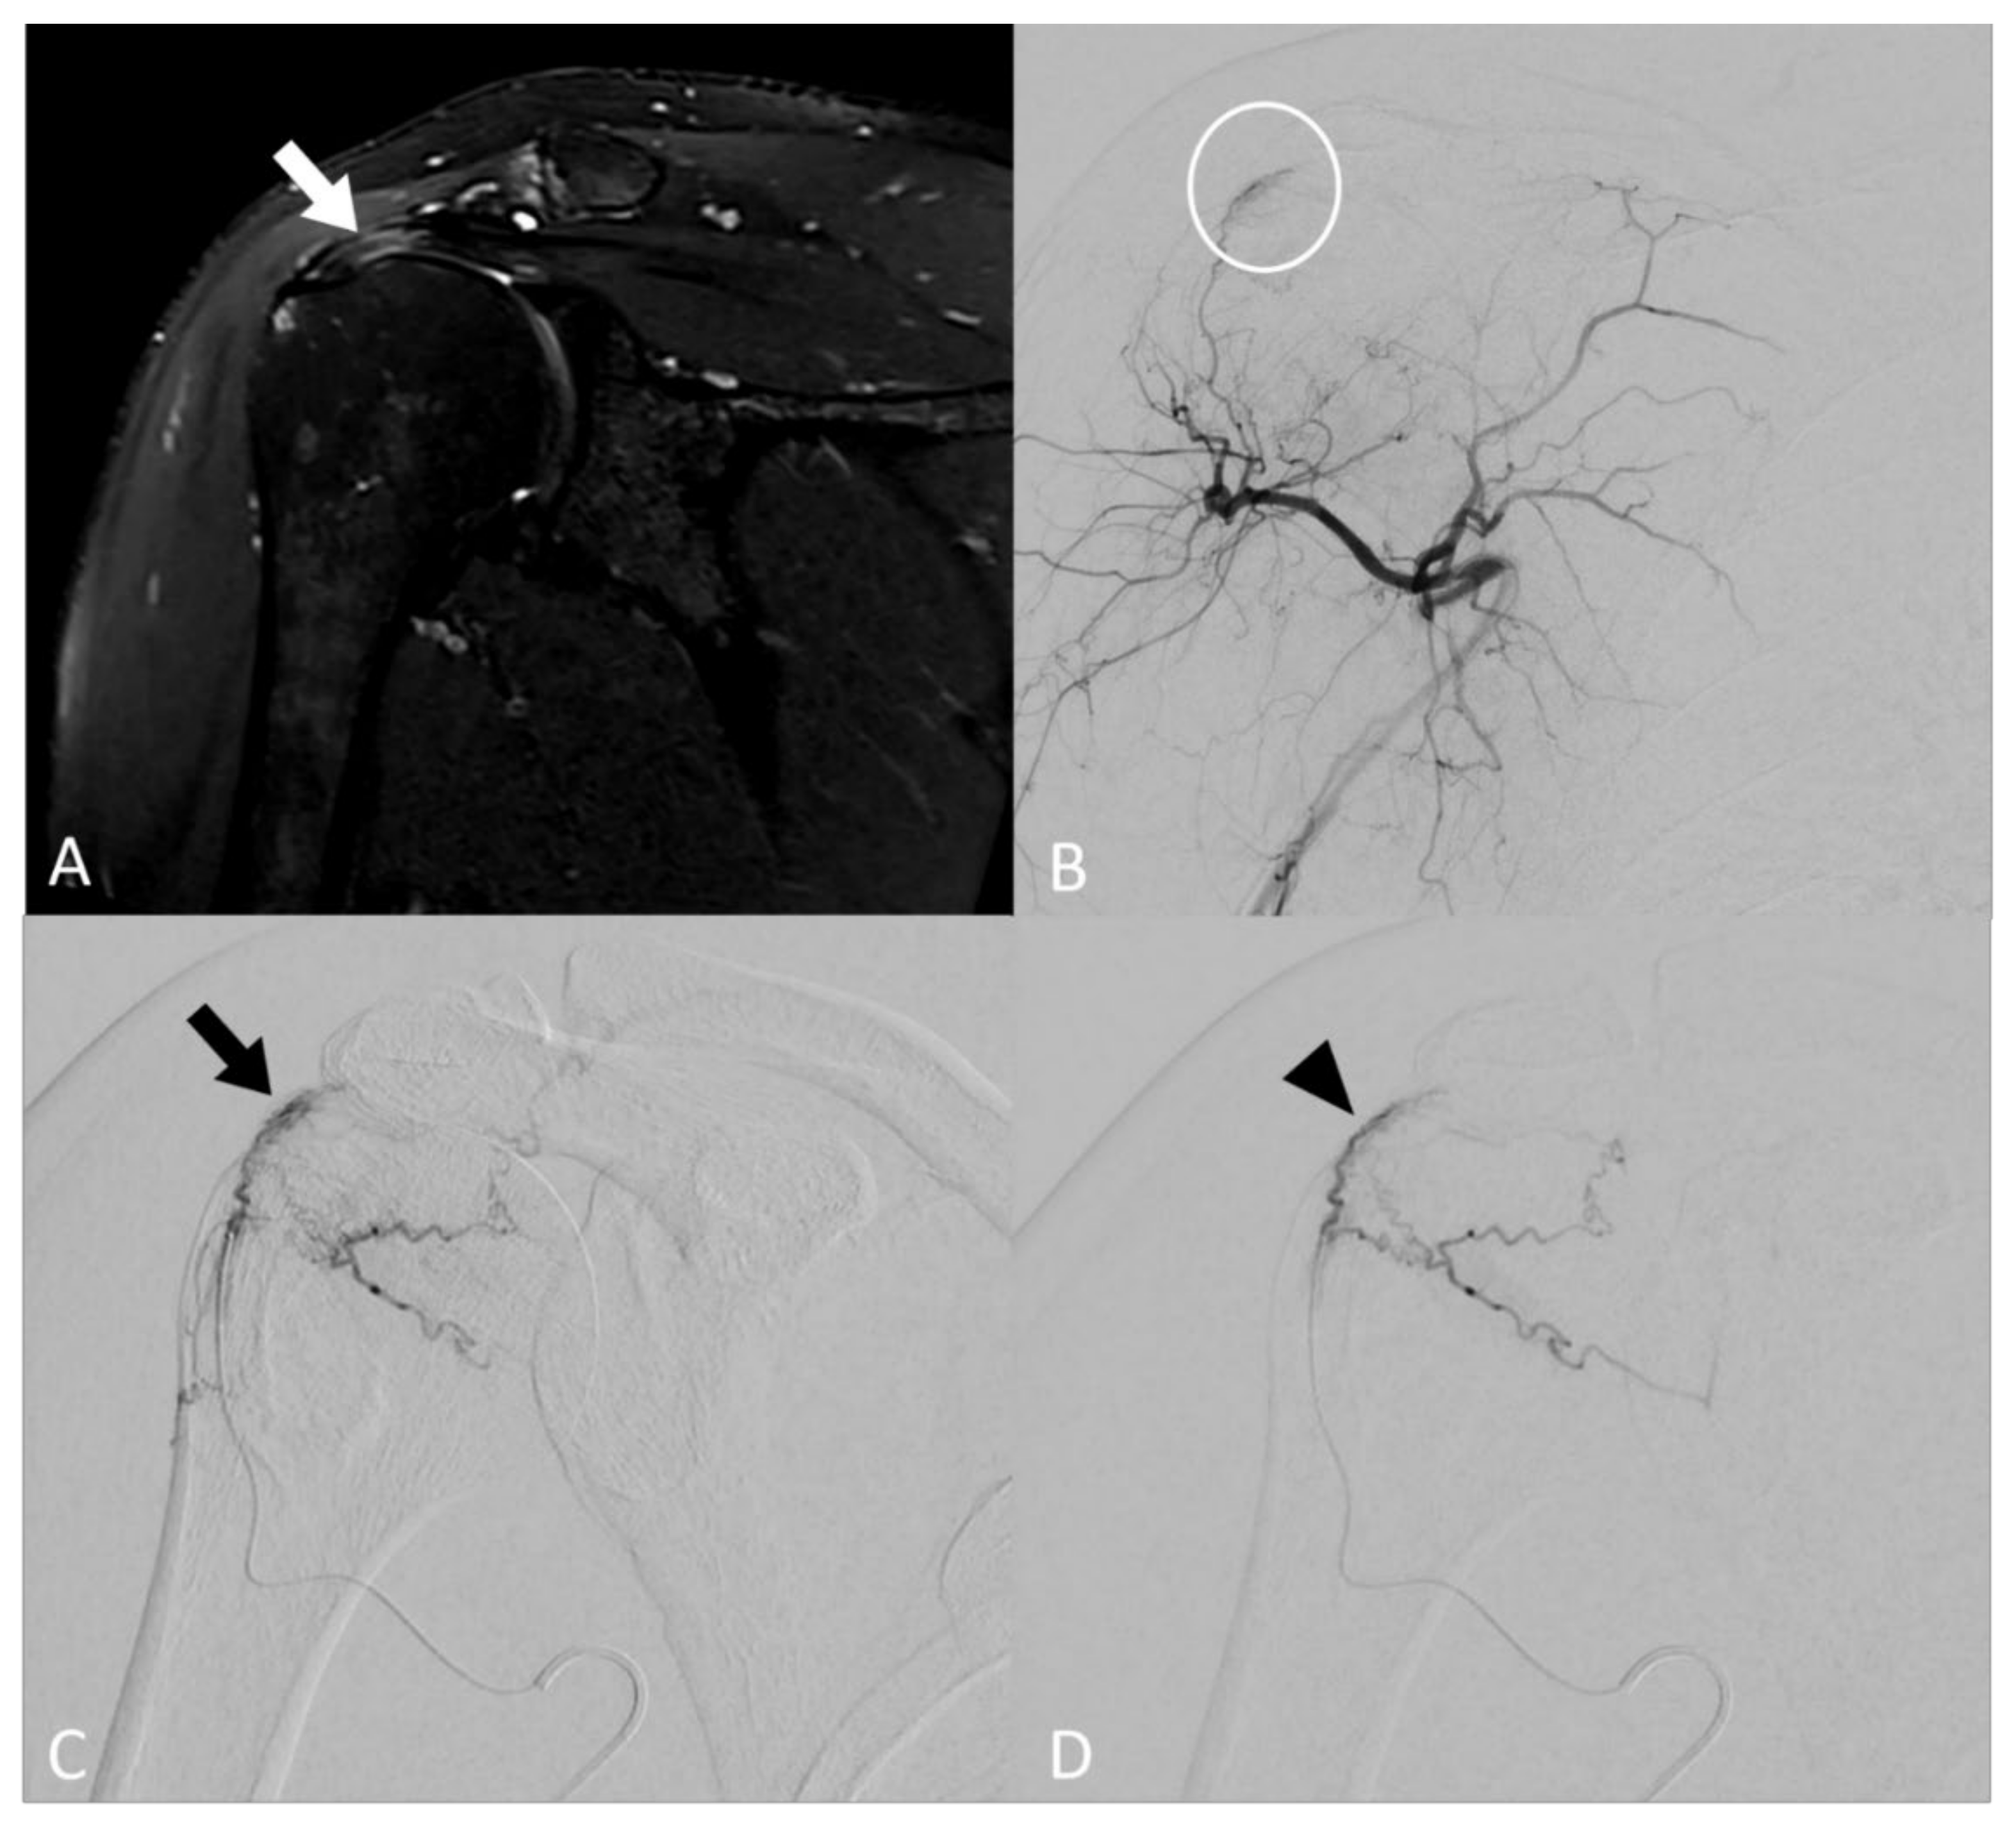

Figure 1. Image of a 46-year-old patient with rotator cuff tendinobursitis refractory to conventional treatment. (A) On baseline coronal T2 fat-sat MR imaging, injury appears as a hypersignal of supraspinatus tendon (white arrow). (B) The digital subtracted angiography (DSA) from the ostium of the posterior circumflex humeral artery confirmed pathological neovessel development in the area supplying the supraspinatus tendon (white circle). (C) DSA after selective microcatheterization of the pathological branch confirmed the “tumor-like” blush (black arrow). (D) DSA after embolization using microspheres demonstrated a decrease in the vascular blush (black arrowhead) that persisted, considering that the collaterals may be at risk of non-targeted embolization complications.

When neovessels were detected, embolization was carried out using calibrated microspheres of 100–250 µm (Embozene®, Boston Scientific Corporation, Malborough, MA, USA) diluted to the eightieth. The solution was loaded in a 1 ml syringe and injected 0.1 mL per 0.1 mL. A maximum volume of 4 mL of diluted particles (i.e., 0.05 mL of microspheres) solution was injected to limit off-targeted ischemic complications. Cutaneous collaterals were protected using an icepack on the skin. The patient related during the procedure whether the selective injection of iodine contrast reproduced the usual shoulder pain, thus reinforcing the operator to perform embolization in this area. The therapeutic strategy consisted in embolization of the neovessels, whilst carefully maintaining the larger vascular supply to off-target structures, such as the skin and bones. The disappearance of neovessels, i.e., the reduction of the tumor blush with a “dead tree” appearance, described in the literature [26] as “pruning embolization”, was considered the goal to be achieved with the embolization procedure. When collateral openings were reported during the embolization process, only a decrease of the blush was reached to avoid off-targeted embolization complications (Figure 1).

3.2. Angiographic Findings

The technical success was 100%, as MSK embolization by selective catheterization of at least one feeder artery with reduction of the vascular blush in angiography was achieved in all 15 patients (Table 2). The presence of neovessels was reported in all patients (100%). MSK embolization was performed by a homolateral radial approach in 14 patients (93%); for the last patient, MSK embolization was performed via a femoral arterial access because of a radial spasm. The median number of arteries treated per procedure was 2 (IQR: 2–3), with a total of 35 arteries treated. The targeted artery depended on the blush location and was the thoracoacromial artery in 8 patients (23%), the anterior circumflex humeral artery in 11 patients (31%), the posterior circumflex humeral artery in 9 patients (26%) and the scapular circumflex artery in 7 patients (20%). The median total volume of diluted microspheres solution was 3.0 mL (IQR: 2.4–3.5). The median procedure time was 106.0 min (IQR: 91.0–114.5), with a median scopy time of 32.1 minutes (IQR: 26.4–34.1).